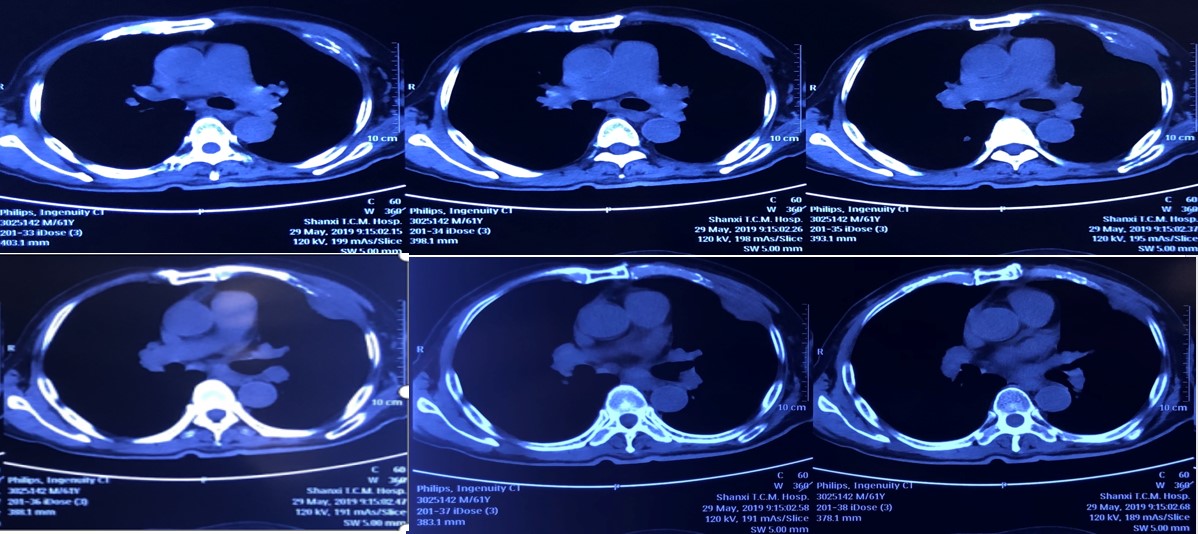

2019年5月5日使用信迪利单抗1周期后复查CT,可见胸腔积液消失,肋骨及胸膜处病灶缩小明显,效果十分显著(图2)。2.jpg

图2. 2019年5月5日使用信迪利单抗1周期后的CT复查结果